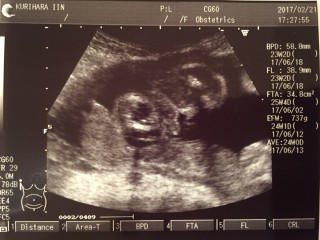

24週3日のエコー写真です。

推定体重は783g。

唇をとんがらせてますw